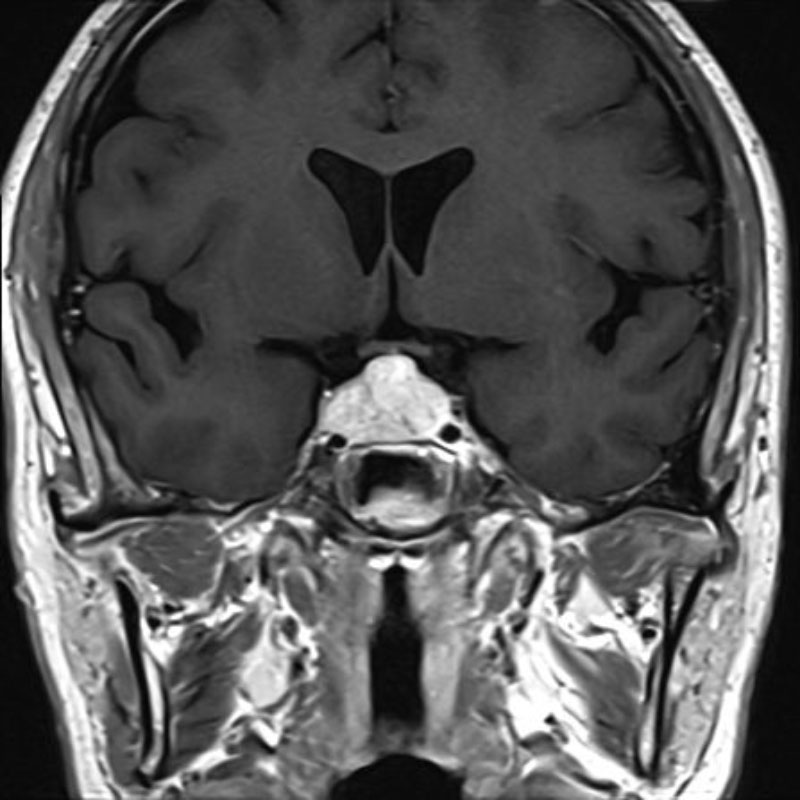

断層撮影

手術前2